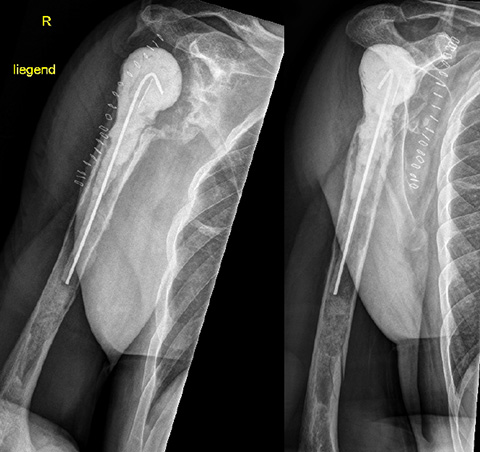

Pre-op

- 49-year-old male

- Height 187 cm / Weight 107 kg

- After three revisions of a right reverse shoulder prosthesis the component got infected with subsequent stem loosening (cemented revision stem)

- Infection treatment with cement spacer

- Target: Reimplantation of cementless RSA with individualized custom-made reverse glenoid baseplate

- CT-Scan image a/p with cement spacer

- Large glenoid defect

- Large humeral bone defect